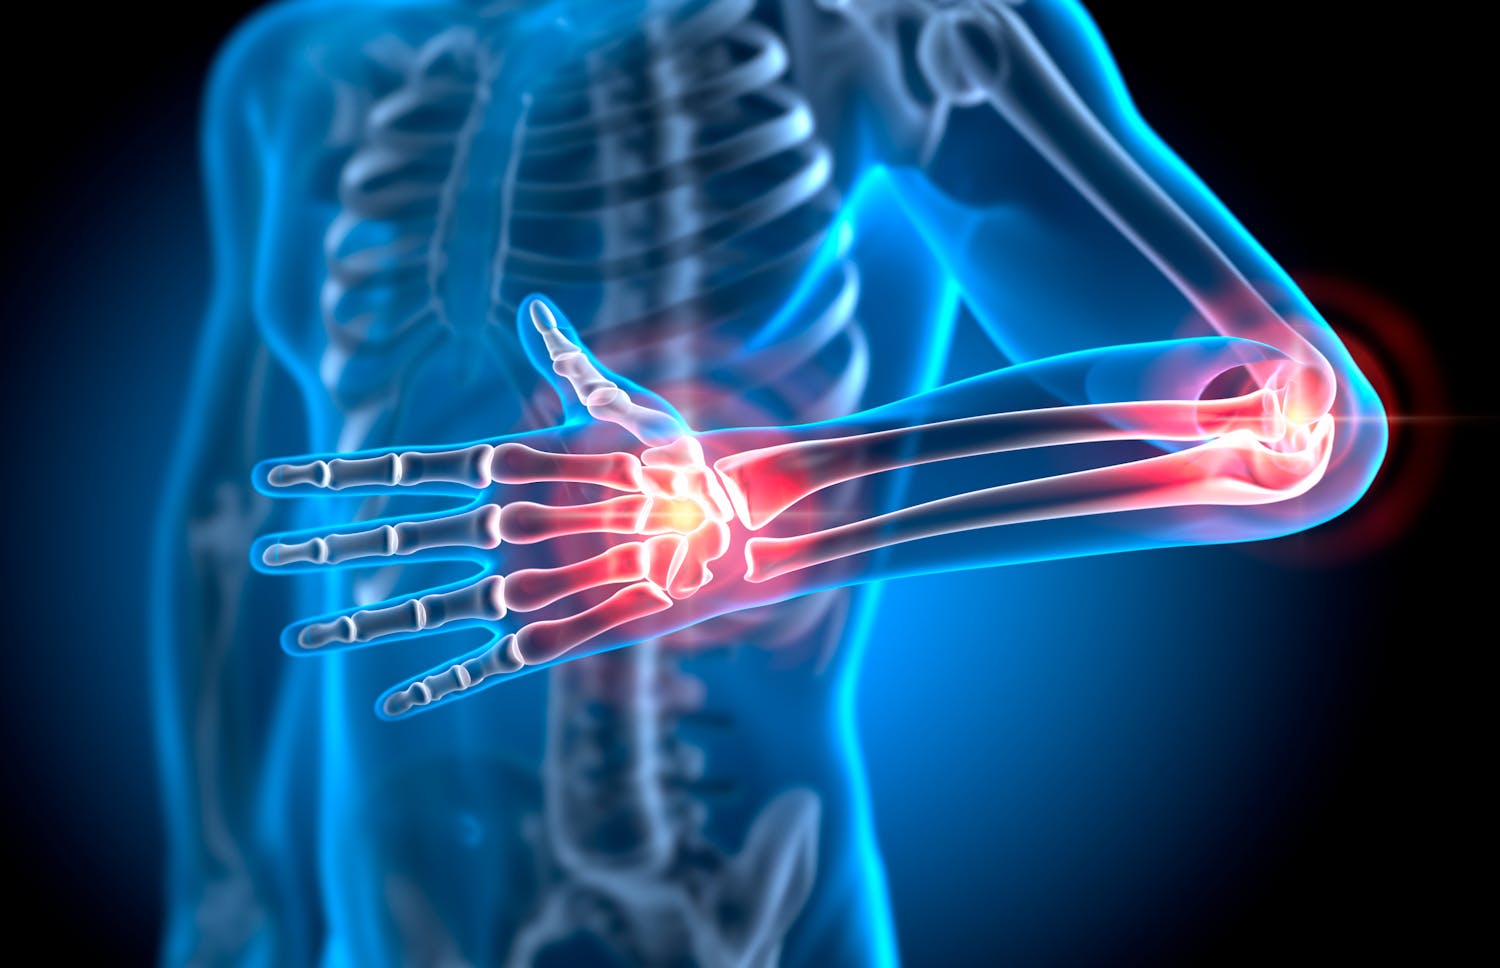

Le cubitus est un acteur clé de la mobilité du bras. Cet os discret, souvent éclipsé par l’humérus et le radius, joue un rôle essentiel dans nos gestes du quotidien.

Le cubitus est un acteur clé de la mobilité du bras. Cet os discret, souvent éclipsé par l’humérus et le radius, joue un rôle essentiel dans nos gestes du quotidien.  Read MoreSanté Magazine